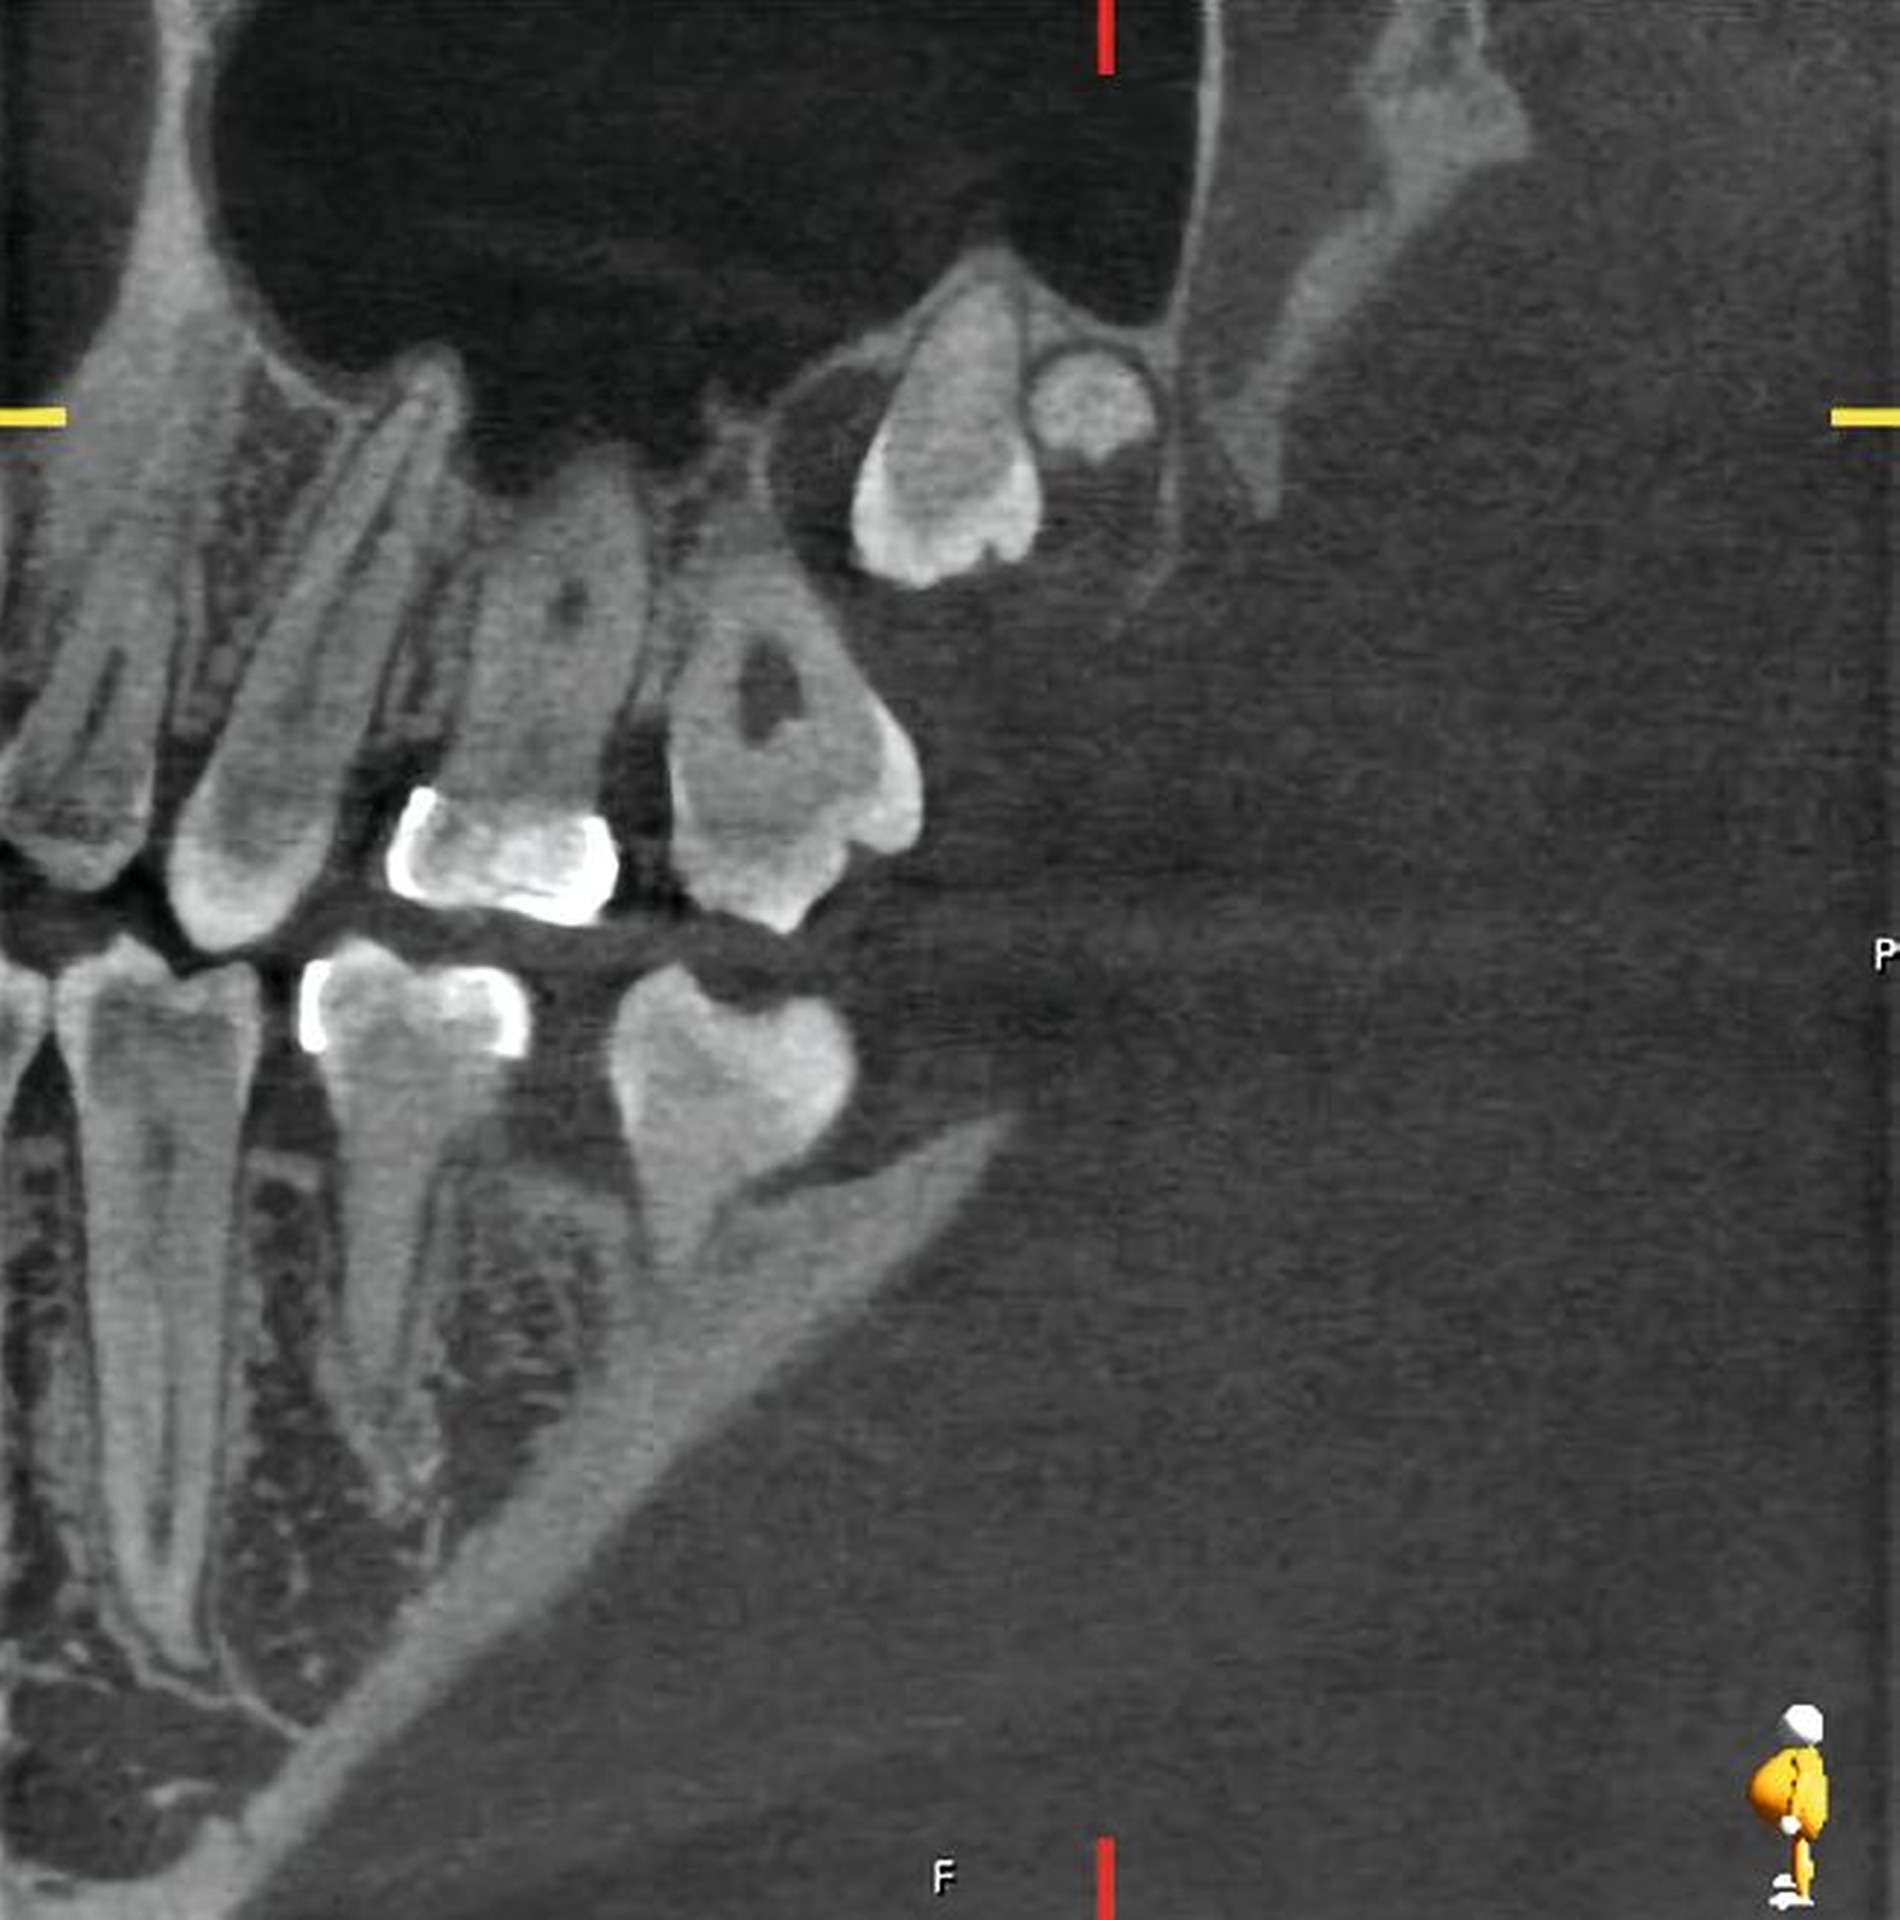

Im Oberkiefer zeigte sich auf der linken Seite neben dem hoch verlagerten und retinierten Zahn 28 ein ebenfalls hoch verlagerter und retinierter Zahn 29 (Abbildung 4) mit enger Lagebeziehung zur Kieferhöhle. Im rechten Oberkiefer erkennt man neben dem hoch verlagerten und retinierten Zahn 18 eine Doppelanlage des Zahnes 19 ebenso in enger Lagebeziehung zur Kieferhöhle (Abbildung 5).